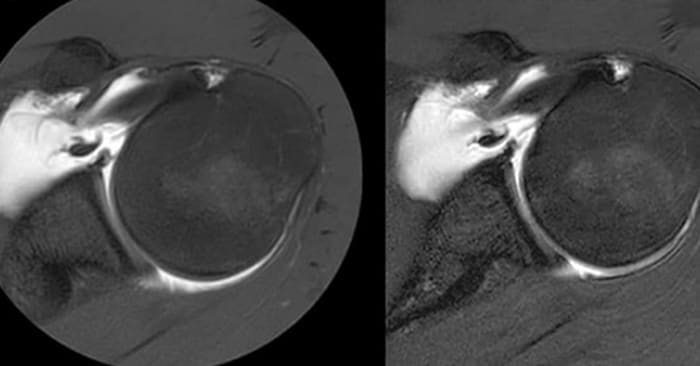

Comparison of axial fat suppressed PD-weighted imaging with (left) and without (right) MultiVane XD in the left shoulder demonstrates imaging with MultiVane XD provides excellent image quality, even in presence of motion.